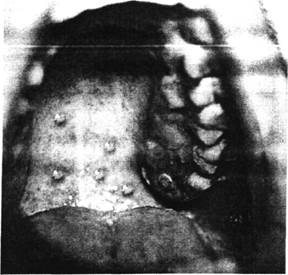

Нередко везикулезные высыпания появляются и на слизистых оболочках полости рта (рис. 1), конъюнктиве глаз, реже - гортани, половых органах. Элементы сыпи на слизистых оболочках нежные, быстро покрываются и пре­вращаются в поверхностные эрозии, при этом может появляться незначительная болезненность. Заживление эрозий наступает на 3-5 день появле­ния высыпаний.

При ветряной оспе высыпания появляются не одновременно, а как бы толчкообразно с промежутками в 1-2 дня. Вследствие этого на коже можно видеть элементы, находящиеся на разных стадиях развития – макуло-папулы, пузырьки, корочки (рис. 2). Это так называемый "ложный полиморфизм" сыпи, характерный для ветряной оспы. Каждое новое высыпание сопровождается и новым подъемом температуры тела, поэтому тем­пературная кривая при ветряной оспе имеет не­правильный вид. На высоте заболевания, что обычно совпадает с максимально выраженным высыпанием, дети могут жаловаться на общее недомогание, нарушение аппетита и ритма сна. Дети раннего возраста становятся раздражитель­ными, капризными, их беспокоит зуд кожи. Сим­птомы интоксикации более выражены при обиль­ной сыпи и у детей раннего возраста.